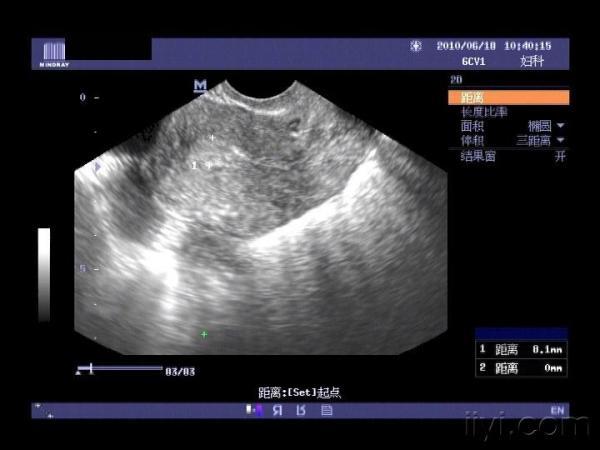

大家来帮我看看,右边这个是输卵管积水还是卵巢囊肿?

右侧附件区的包块。

假如我下结论就下附件区囊性占位、保守点